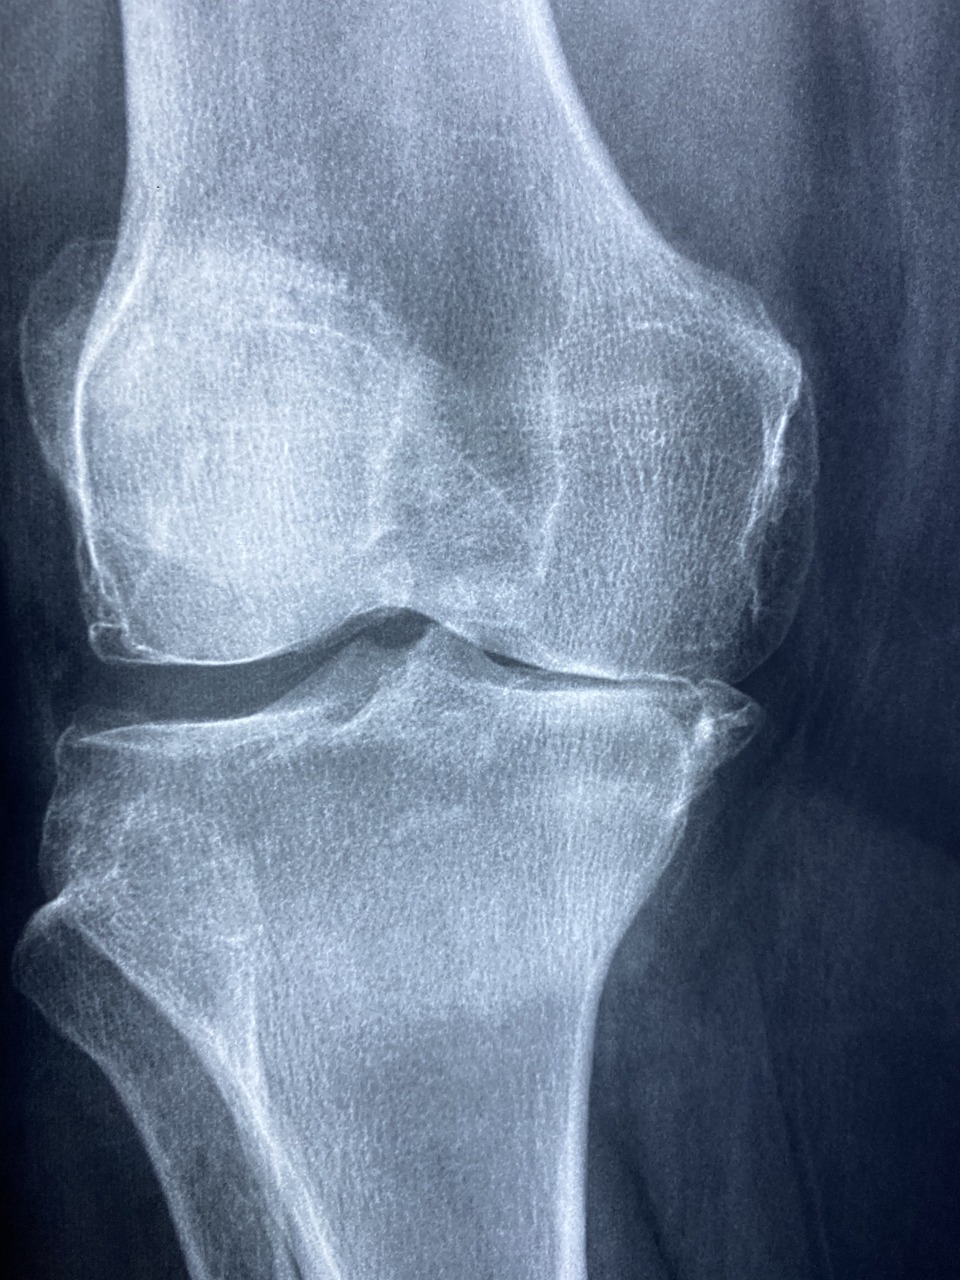

콘드로이친(Condroitin)은 연골 건강과 관련된 보충제로 사용되는 물질 중 하나입니다. 주로 관절 건강을 유지하고 연골 손상을 예방하기 위해 사용됩니다. 콘드로이친은 연골 조직 내에서 발견되는 주요 성분 중 하나로, 그 주요 기능은 연골의 탄력과 내구성을 유지하는 것입니다.

콘드로이친은 연골 조직의 주요 성분 중 하나로, 연골을 건강하게 유지하고 손상을 예방하는 역할을 할 수 있습니다. 연골은 관절에서 뼈를 보호하고 움직임을 부드럽게 만드는 중요한 역할을 합니다.

연령이 들어감에 따라 연골 조직은 손상되기 쉽습니다. 콘드로이친은 연골의 건강을 유지하고 미래의 연골 손상을 예방하는 데 도움을 줄 수 있습니다.